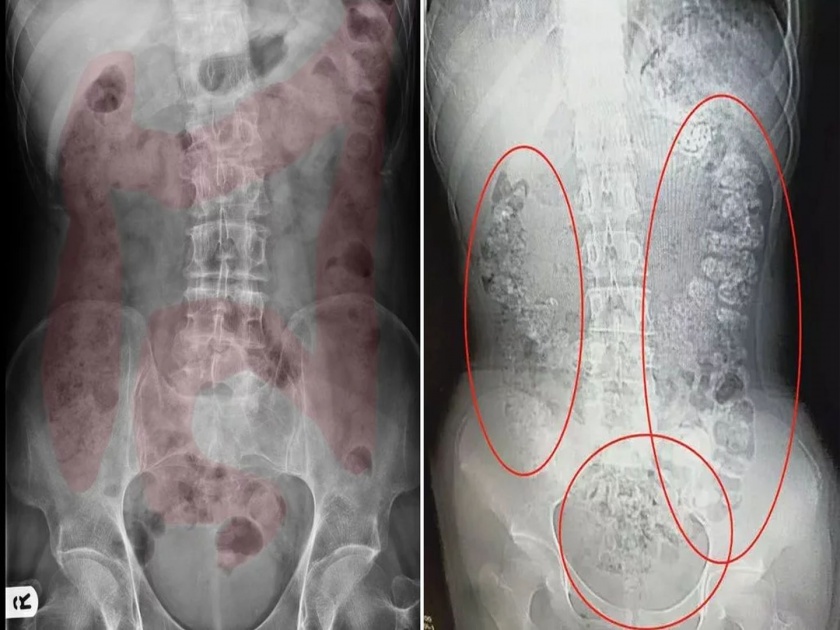

डॉक्टरांनी जेव्हा तिचं सिटी स्कॅन केलं तेव्हा तिच्या पोटात काही दिसलं. पोटातील वस्तू पाहून डॉक्टरही हैराण झाले. त्यानंतर डॉक्टरांनी मुलीला तिच्या खाण्या-पिण्याबाबत विचारणा केली. तेव्हा तिने सांगितले की, पाच दिवसांपूर्वी तिने एक कप बबल टी घेतली होती.

पण डॉक्टर तिच्या बोलण्याने संतुष्ट झाले नाहीत. कारण तिच्या पोटात त्यांना १०० पेक्षा अधिक बबल टी बॉल्स आढळले. डॉक्टरांचा अंदाज होता की, ही मुलगी दररोज एक कप बबल टी सेवन करत असेल आणि त्यामुळेच तिच्या पोटात टॅपिओका बॉल्स जमा झालेत.